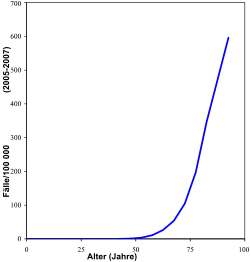

Рак предстательной железы — одно из наиболее распространённых злокачественных новообразований у мужчин. Ежегодно в мире выявляется свыше 400 000 случаев рака предстательной железы; в ряде стран он занимает в структуре онкологических заболеваний 2-е или 3-е место после рака лёгких и рака желудка[2] (так, в Европе в 2004 году заболеваемость раком предстательной железы составляла 214 случаев на 100 000 мужчин, в результате чего рак простаты занимал 2-е место среди основных причин смерти от рака у мужчин, опережая рак лёгких и колоректальный рак[3]).

Согласно данным общемировой статистики в 2012 году рак простаты зафиксирован у 1,1 млн мужчин, и одновременно привел к 307 тыс. летальных исходов[4]. Рак предстательной железы является причиной почти 10 % смертей от рака у мужчин и служит одной из главных причин смерти у пожилых мужчин. В США рак предстательной железы является третьей по частоте причиной смерти от злокачественных опухолей[5].

В России заболеваемость раком простаты занимает 7-е—8-е место (составляя около 6 %). У мужчин старше 60 лет это — наиболее часто встречающееся злокачественное новообразование. Особенностью рака простаты в России и других странах СНГ является поздняя диагностика, когда опухоль диагностируют на III—IV стадии[2]. В период с 1999 по 2009 годы показатель заболеваемости раком предстательной железы в России вырос в 2,8 раза (первое место среди злокачественных новообразований)[6].

- пожилой возраст (более 75 % случаев рака простаты диагностируется у мужчин старше 65 лет, а на мужчин моложе 60 лет падает лишь 7 % случаев заболевания);

Эпидемиология

По состоянию на 2012 год рак предстательной железы является вторым наиболее часто диагностируемым раком (у 15% всех мужчин) и шестой по значимости причиной смерти от рака у мужчин во всем мире. В 2010 году он привел к смерти 256 000 человек по сравнению с 156 000 смертей в 1990 году. Показатели рака предстательной железы широко варьируются по всему миру. Хотя показатели сильно различаются между странами, он наименее распространен в Южной и Восточной Азии, и более распространен в Европе, Северной Америке, Австралии и Новой Зеландии.

Более 80% мужчин заболевают раком предстательной железы в возрасте 80 лет. В большинстве случаев рак будет медленно расти и не вызывает особых опасений.